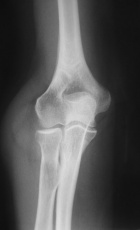

62 y/o female presents with a few months of an increasing left elbow mass, discomfort with activity, relieved by rest

PMH/PSH: Breast cancer treated with lumpectomy, nonsmoker

PE: Large nontender mass anterior L elbow, only a few degrees loss of ROM at elbow, no LAN, neurovasculary intact